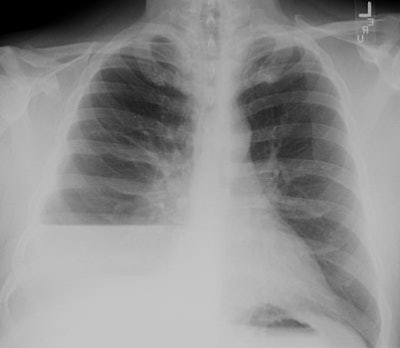

CXR: On CXR the abnormality can be localized to the pleural space because of its lenticular shape (forms obtuse angles with the chest wall, while a lung abscess is usually round with acute angles). An air-fluid level associated with an empyema is usually longer on the lateral film [7].| Empyema:

The CXR demonstrates a large, lenticular shaped air-fluid

level in the

right pleural space |